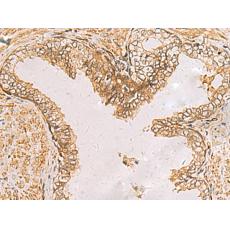

IHC positive control:

Human liver cancer and Human prostate cancer

IHC Recommend dilution:

50-200